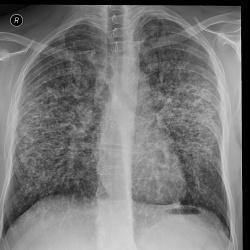

Пациент 63 года. Жалобы на слабость, кашель с мокротой.